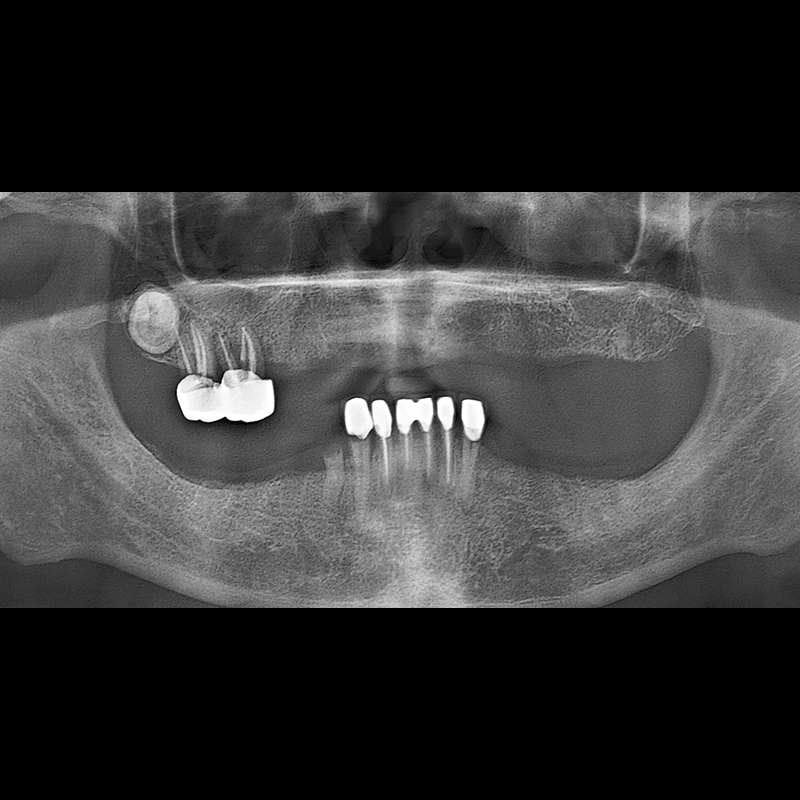

BEFORE AFTER

种植牙前后的照片 2025.05.30

在缺失的牙齿部分和难以挽救的牙齿位置植入了种植牙。